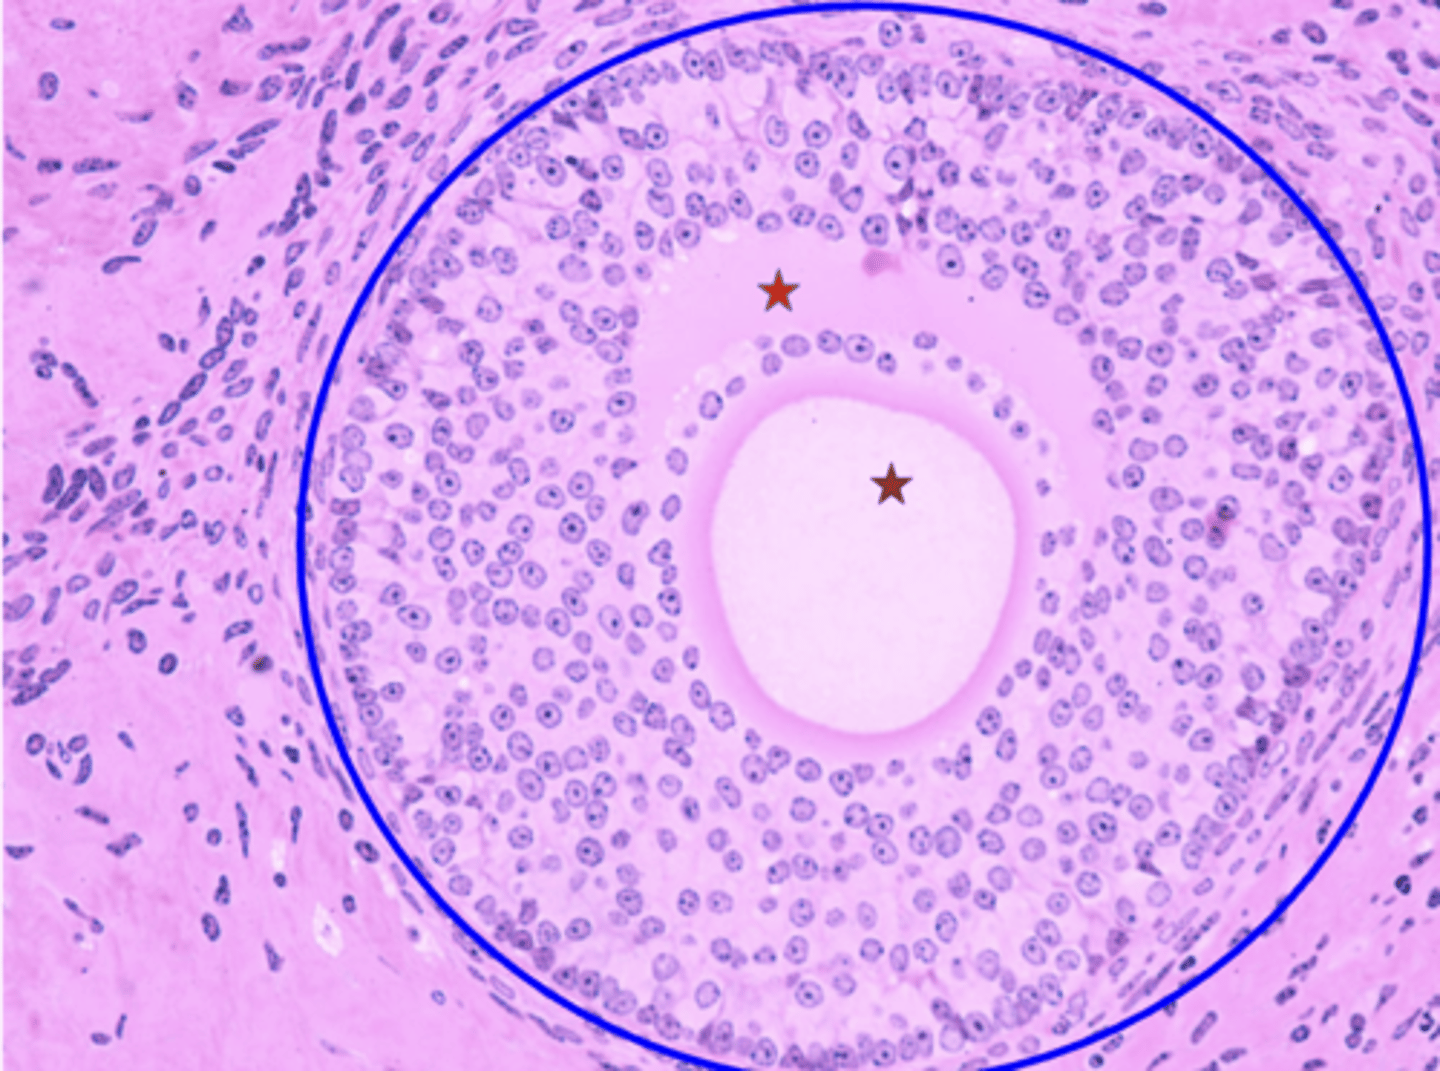

Germinal epithelium

What is the black arrow?

Tunica albuginea

What is the red arrow?

Primordial follicles

What is the green circle?

Multilaminar primary follicle

What is the blue outline?

Primary oocyte

What is the red star?

Simple cuboidal epithelium

Tissue type of germinal epithelium?

Fibrous layer of connective tissue

Tissue type tunica albuginea?